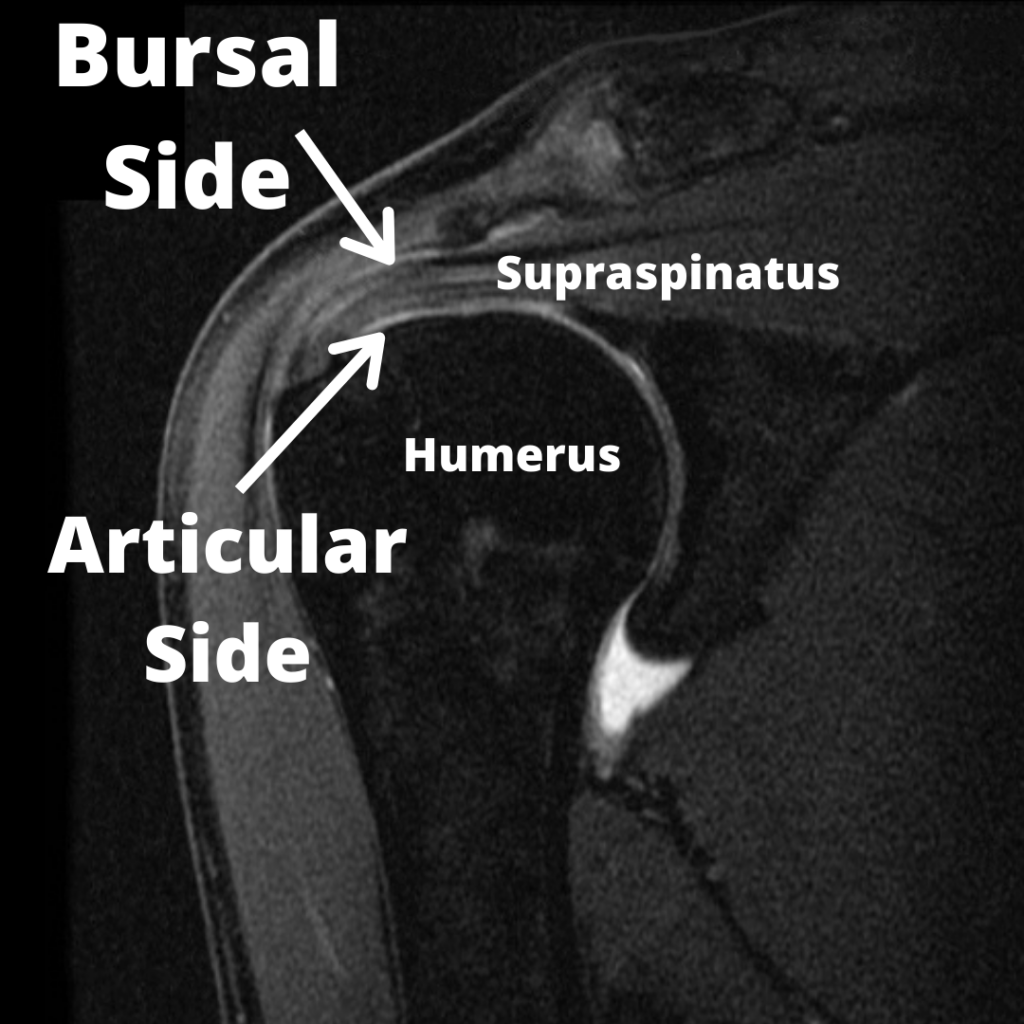

Your rotator cuff isn't one thing. It's a group of four muscles and their tendons that work together to stabilize your shoulder joint. Think of it like a muscular cuff surrounding the ball-and-socket joint of your shoulder, keeping the upper arm bone (humerus) centered in the socket (glenoid).

The four muscles are the supraspinatus, infraspinatus, teres minor, and subscapularis. When they work properly, you can rotate your arm, lift it overhead, and perform thousands of movements without thinking about it. When something goes wrong, you feel it immediately.

Over decades of use, these tendons develop changes. Microtears occur. Fibers fray. The tissue develops small defects. In the language of radiology, these become "abnormalities."

But here's where the disconnect happens. The radiologist describes these changes precisely because they're trained to report everything they see. That's their job. But "abnormal" in the imaging sense doesn't equal "abnormal" in the clinical sense—meaning it doesn't automatically mean something is wrong with how your shoulder functions.

But many of these "tears" are more accurately described as normal age-related structural changes. The tissue hasn't torn apart in the traumatic sense. Fibers have disrupted, edges have frayed, the tissue has developed small defects. These are predictable, expected changes that happen to nearly everyone over time.

The study authors propose using more precise, less value-laden terminology:

- Lesion (instead of tear)

- Defect (instead of tear)

- Fraying (describing exactly what's happening)

- Disruption (describing fiber separation)

- Structural alteration (describing what changed)

- Degeneration (describing age-related changes)